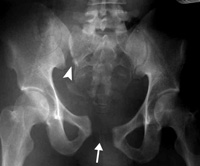

X-ray shows an unstable pelvic fracture with disruption of the pubis (arrow) and sacroiliac joint (arrowhead).

Reproduced with permission from JF Sarwark, ed: Essentials of Musculoskeletal Care, ed 5. Rosemont, IL, American Academy of Orthopaedic Surgeons, 2016.